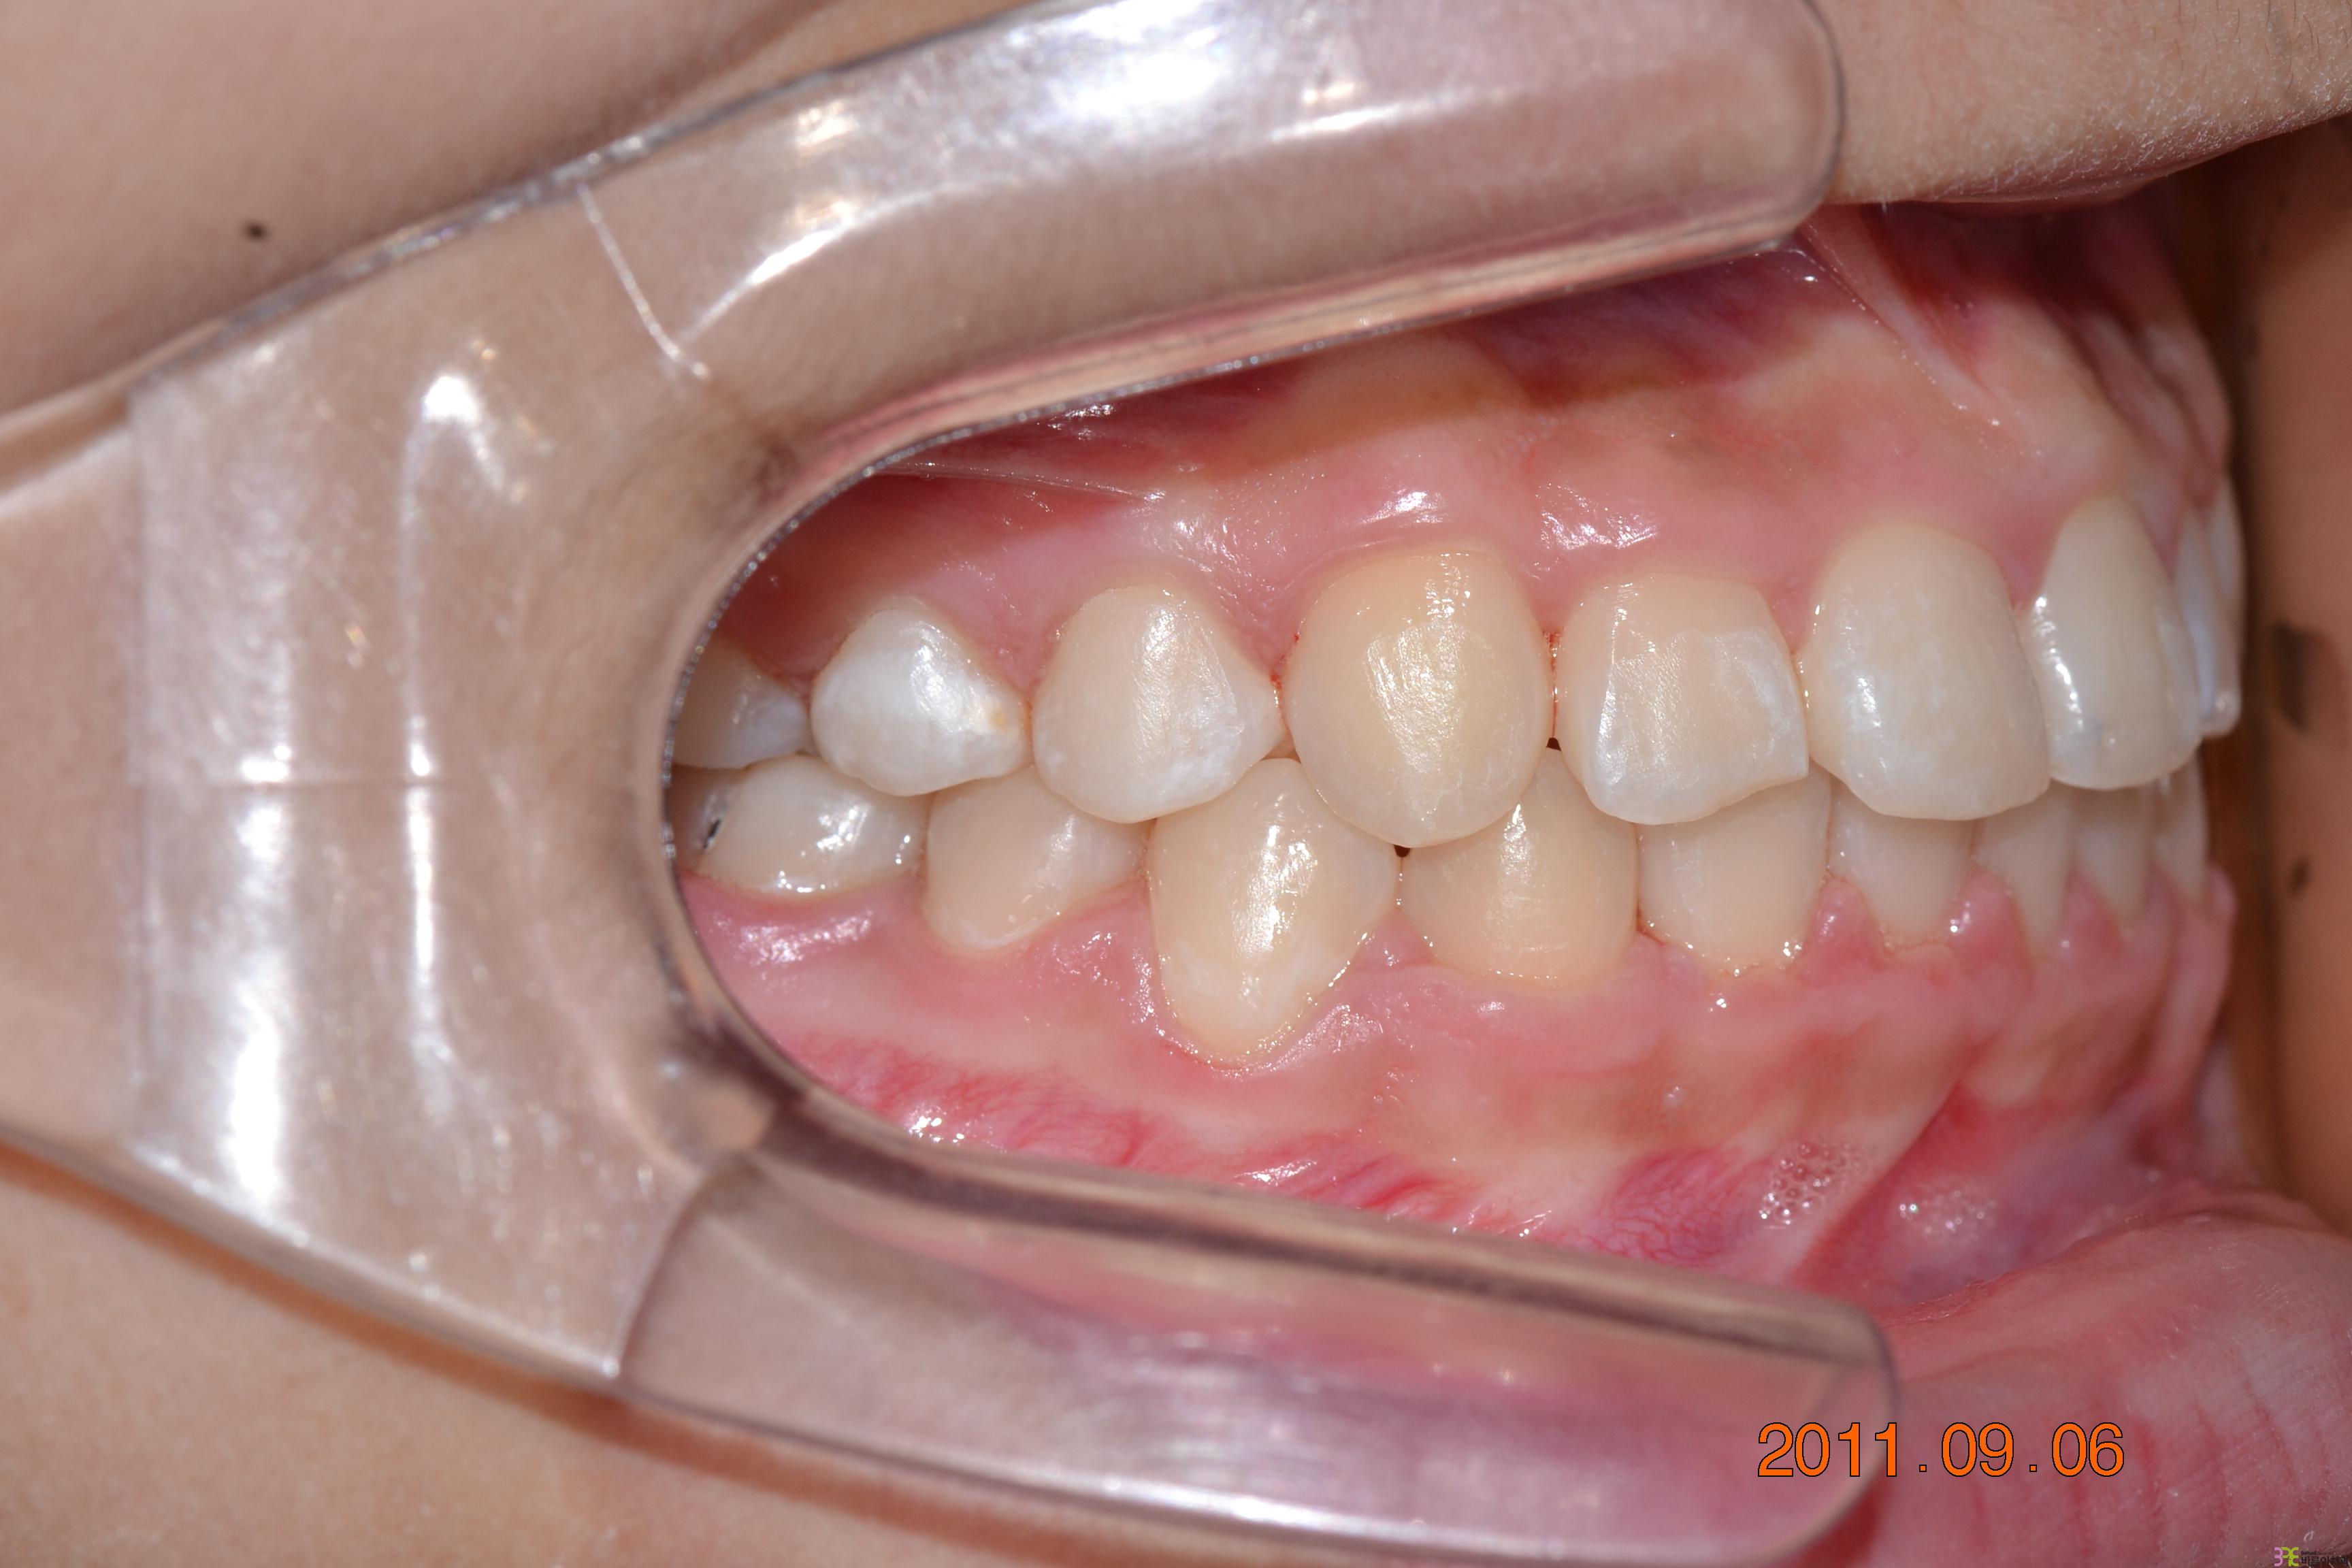

치료명

덧니교정

치료기간

1년 9개월